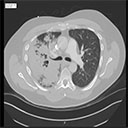

View Case #24001

A man in his 60s presents with progressive shortness of breath.